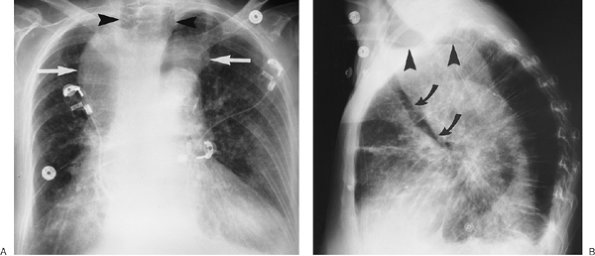

FIGURE 6-4. Morgagni hernia. PA (A) and lateral (B) chest radiographs show colon, filled with air and stool (arrows), herniating into the anterior mediastinum through a congenital defect in the anteromedial diaphragm.

FIGURE 6-10. Benign cystic thymoma. A: PA chest radiograph shows an abnormal left mediastinal contour (arrow). B: Lateral view shows a round, circumscribed mass with a high-attenuation rim in the anterior mediastinum (arrows). C: CT scan shows a mass of soft tissue attenuation (T) with dense rim calcification anterior to the ascending aorta.

FIGURE 6-11. Benign thymoma. A: PA chest radiograph shows an abnormal left mediastinal contour (arrow). B: CT scan shows soft tissue anterior to the ascending aorta in the expected location of the thymus gland (arrow). C: CT scan inferior to (B) shows that the thymic soft tissue (T) is focally enlarged on the left.